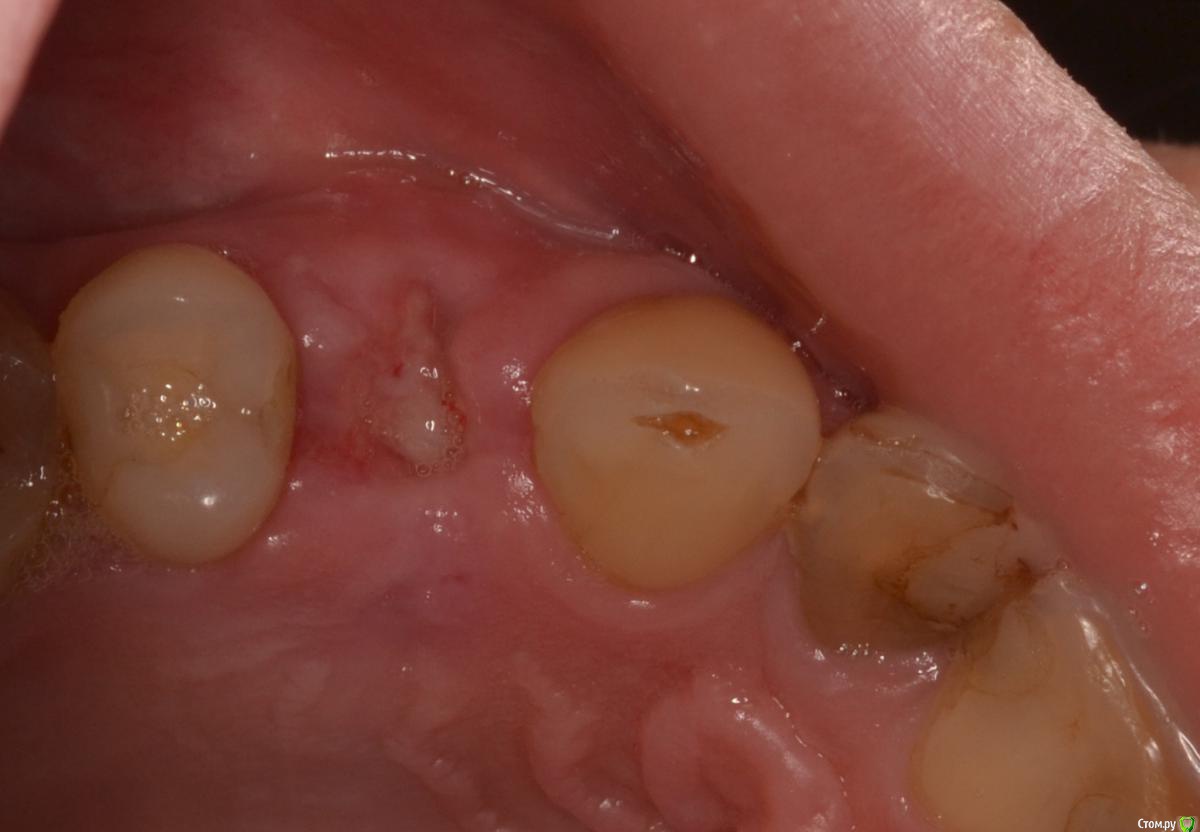

Военный Врач Опубликовано 5 апреля, 2016 Поделиться Опубликовано 5 апреля, 2016 Удалили и прикрутили. между имплантацией и снятием швов 9 суток. лунку закрывал тканями с бугра 18 Ссылка на комментарий

Военный Врач Опубликовано 5 апреля, 2016 Автор Поделиться Опубликовано 5 апреля, 2016 Торк не позволил ФДМ поставить?торк очень низкий. не будем торопиться Ссылка на комментарий

Военный Врач Опубликовано 5 апреля, 2016 Автор Поделиться Опубликовано 5 апреля, 2016 Как приятно читать надписи на родном языке))) И Саш, может стоило чуточку глубже поставить?там и так очень глубоко. просто красиво фотографировать так и не научился... Ссылка на комментарий